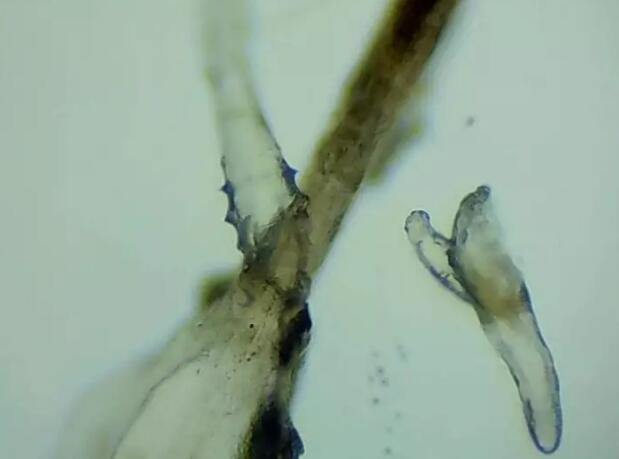

厦门眼科中心蠕形螨性睑缘炎门诊张丽颖博士后介绍,人体螨虫主要有两种,一种是皮脂螨,主要寄生于皮脂腺和睑板腺内;另一种是蠕形螨,“住”在睫毛毛囊里,晚上从毛囊里爬出来,白天躲在毛囊里产卵。

据介绍,这种疾病确诊主要通过观察睫毛里的螨虫数量联合睑缘及眼表情况共同诊断。一般而言,如果12根睫毛里,有2条或是超过2条的螨虫就可以被确诊。如果检查确实发现较多的蠕形螨感染,建议加上抗螨医治。张丽颖说,发现眼睛干涩、发痒,不要自行用药,建议到医院就诊。如果长期反复多发霰粒肿,要考虑是否存在蠕形螨感染。